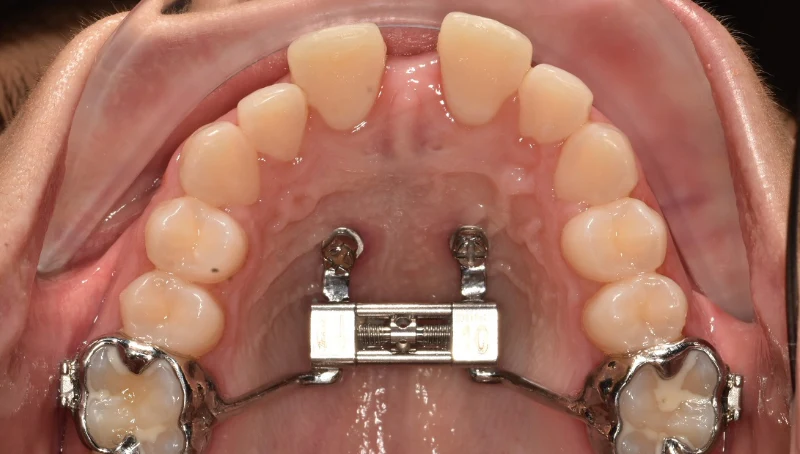

мезиальный прикус, пара зубов на верхней челюсти стоит 2 рядом при этом зубы мудрости сверху выросли нормально

какие шансы просто поставить брекеты и обойтись без операций?

а главный вопрос - по чём сейчас брекеты?

Мне вот зубы мудрости, правда ретинированные, удаляли как раз перед брекетами. Зубы мудрости крупные и сдвигают зубы другие, скучивая их.

Чаще всего рекомендуют их удалить. Потому что после исправления прикуса не факт что зм не поднасрут опять.

По цене у меня в миллионнике так

3д цефалометрия 7к.

Сложное удаление одного зуба 11к. Обычный дешевле будут.

Брекеты и их установка 150к.

Прием перед брекетами и слепок зубов хз сколько.

Посещение 2-4к раз в 2 месяца.

Снятие хз сколько. Ретейнер и или капа на ночь хз.

В любом случае сами брекеты, 150к, это основная сумма. Остальное по мелочи.

В дс 4 выйдет в 2 раза дешевле. Сестра вместо 150 отдала 70 за такие же.